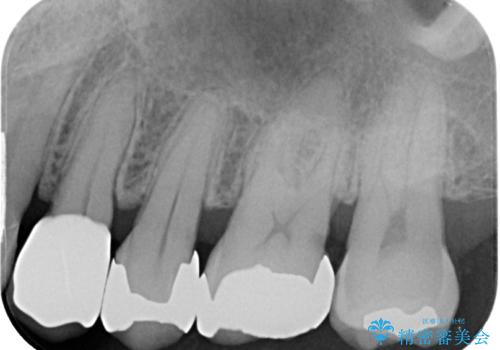

- 治療計画

- 当院で矯正後徐々にセラミックにやり替えたいとのことで来院された患者様です。レントゲン撮影の結果、メタルインレーの不適合を認めました。またメタルインレーの範囲も大きくご自身の残せる歯の量を考慮してオールセラミッククラウンによる補綴治療を行っていくことにしました。

拡大鏡視野下でメタルインレー、虫歯を除去しオールセラミッククラウンに適した形に整えました。